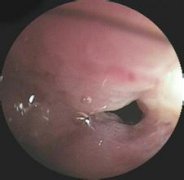

小腸炎是細(xì)菌、病毒、真菌和寄生蟲等引起的炎癥表現(xiàn)。臨床表現(xiàn)主要有腹痛、腹瀉、稀水便或黏液膿血便。部分病人可有發(fā)熱及里急后重感覺,按病程長(zhǎng)短不同,分為急性和慢性兩類。 病因...

1.病史 起病急,發(fā)病前多有不潔飲食史。受冷、勞累,腸道蛔蟲感染及營(yíng)養(yǎng)不良為誘發(fā)因素。 2.腹痛 起病急驟,突然出現(xiàn)腹痛,也??蔀樽钕劝Y狀,多在臍周。病初常表現(xiàn)為逐漸加劇的臍周或...